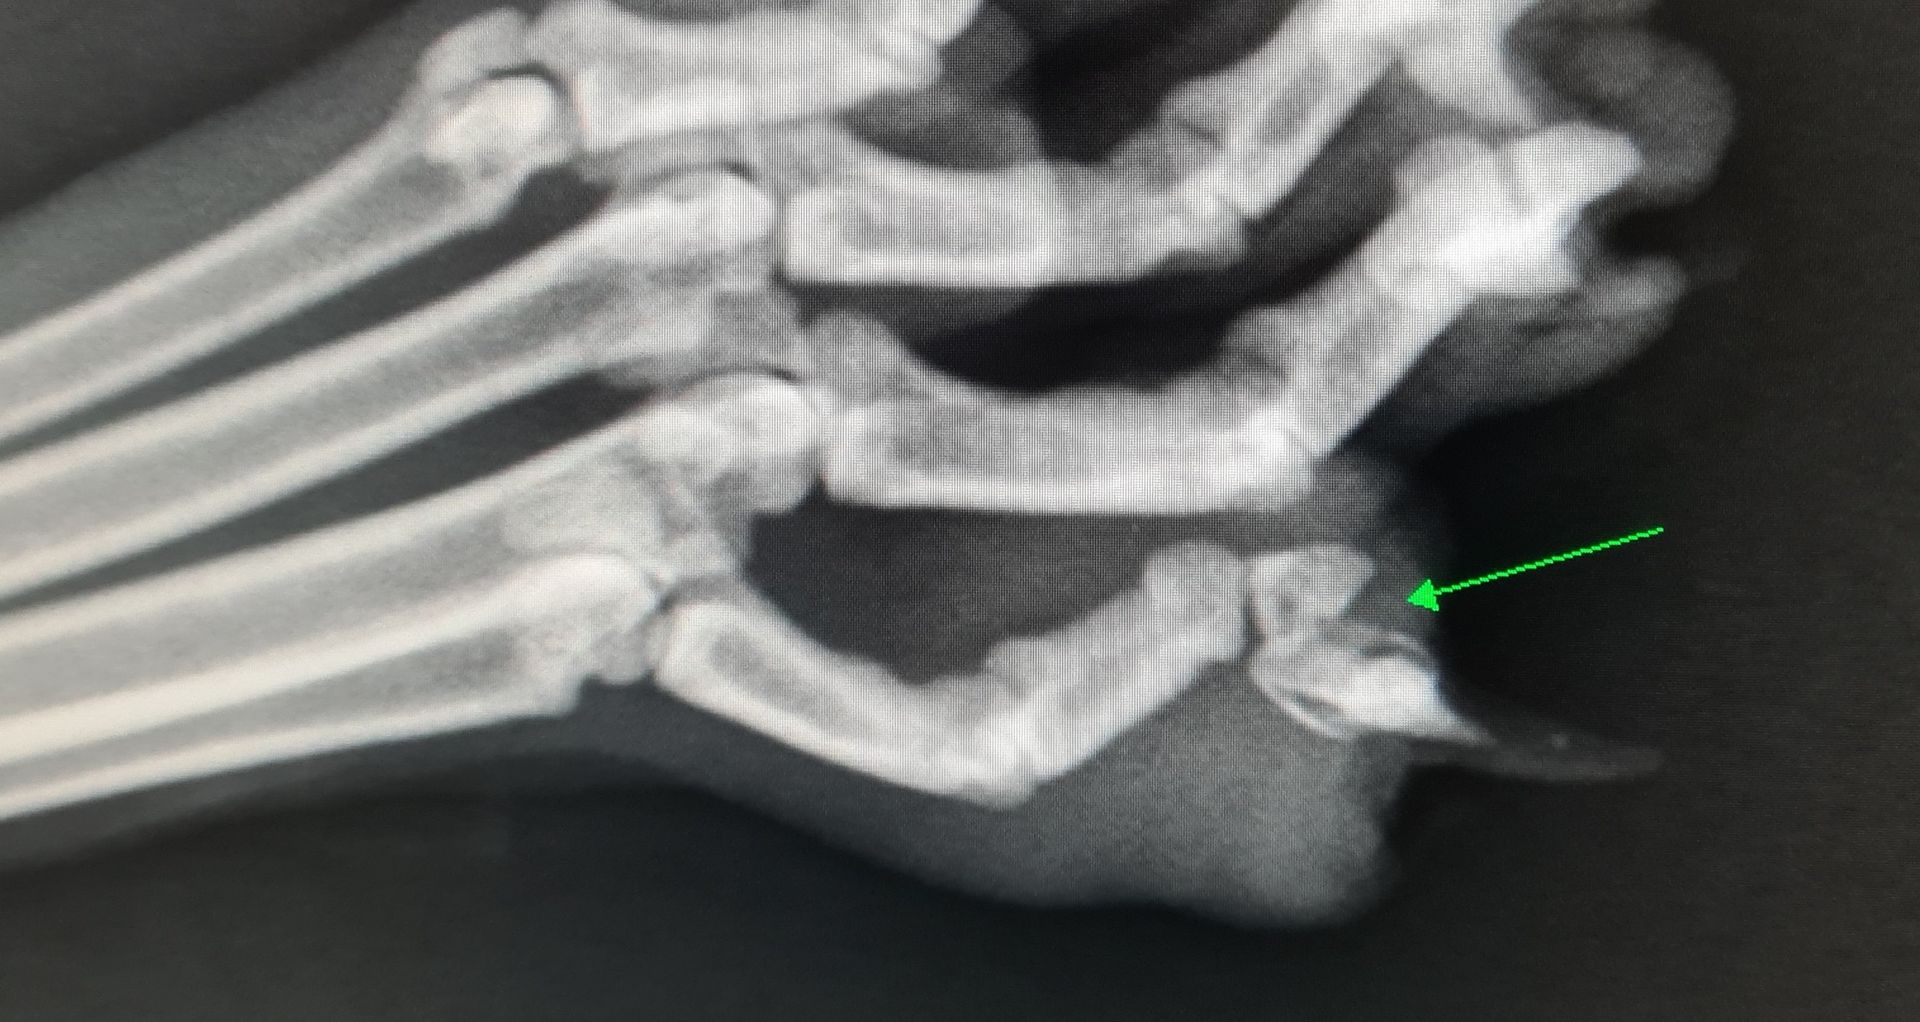

- Radios officielles de dysplasie des hanches ou du coude avec anesthésie